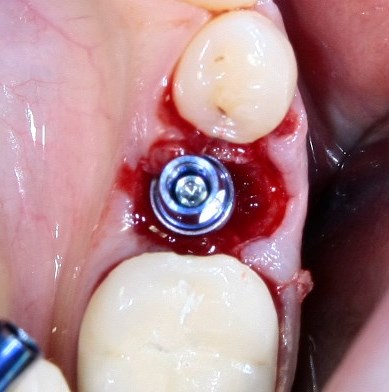

Немедленная имплантация — оптимальное решение в любой клинической ситуации